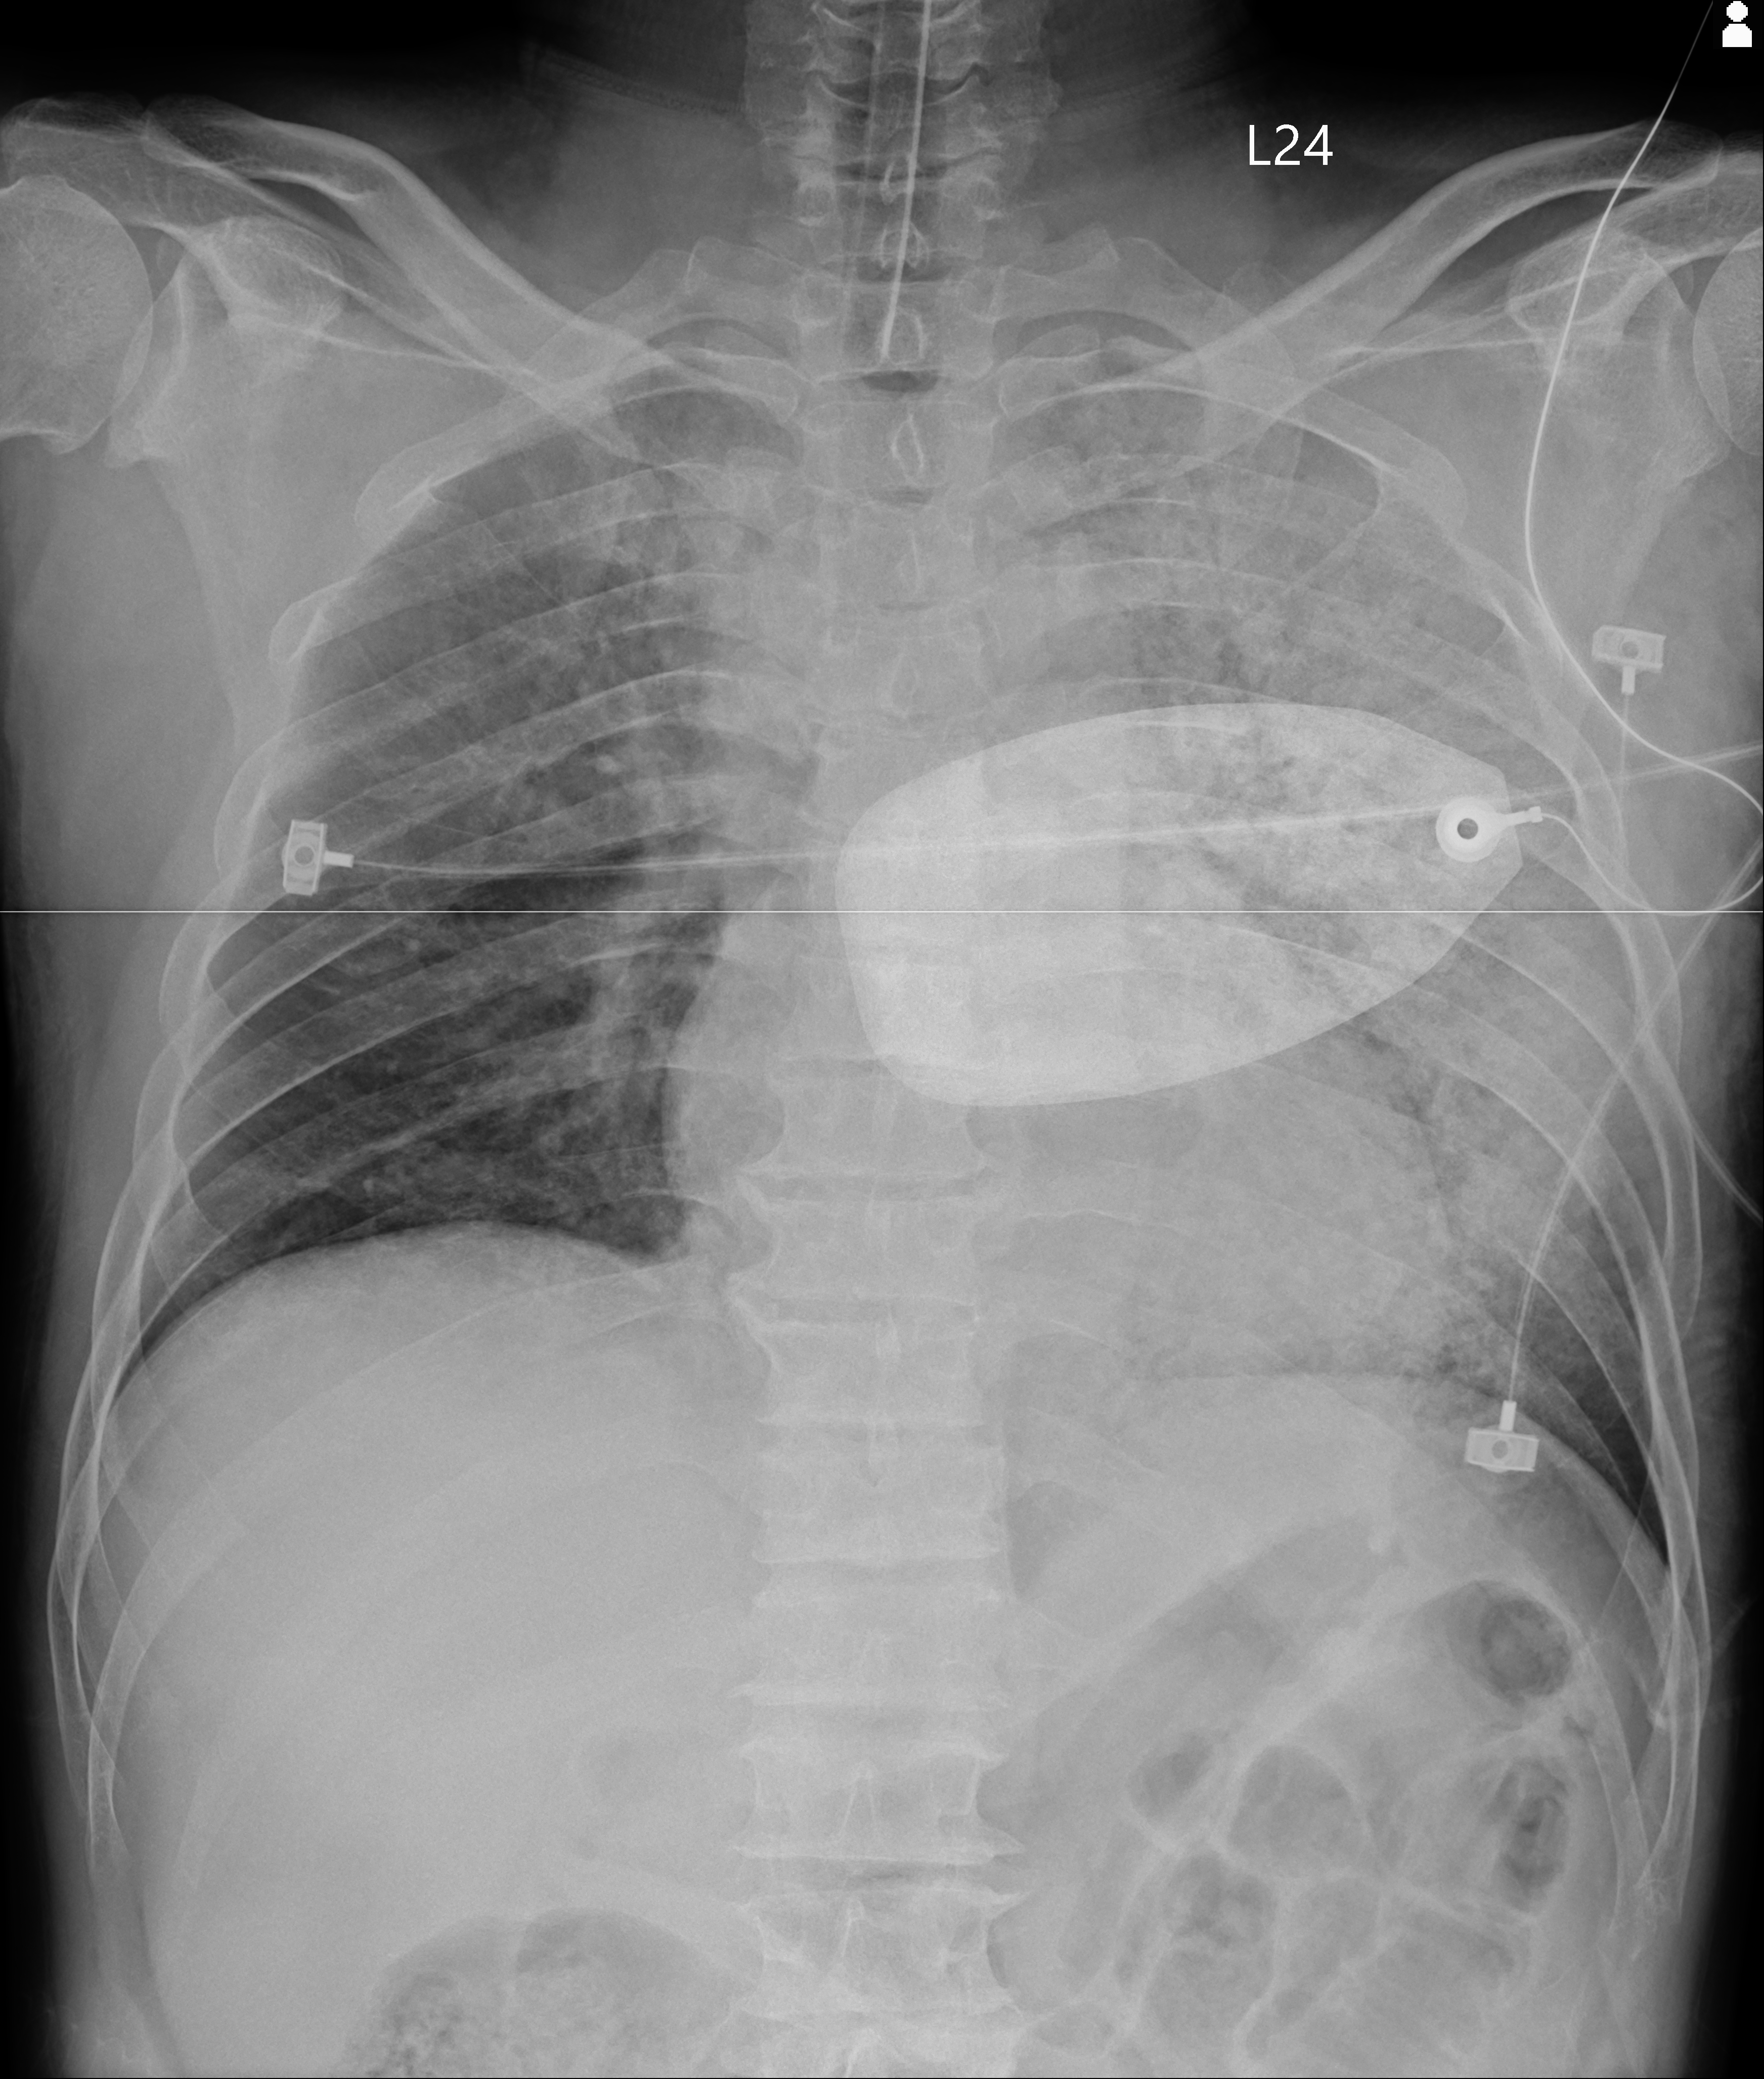

Fig.8可以看到在急診的CXR,左側要whiteout。後續在ICU驗到是Flu B,也通報了流感重症。